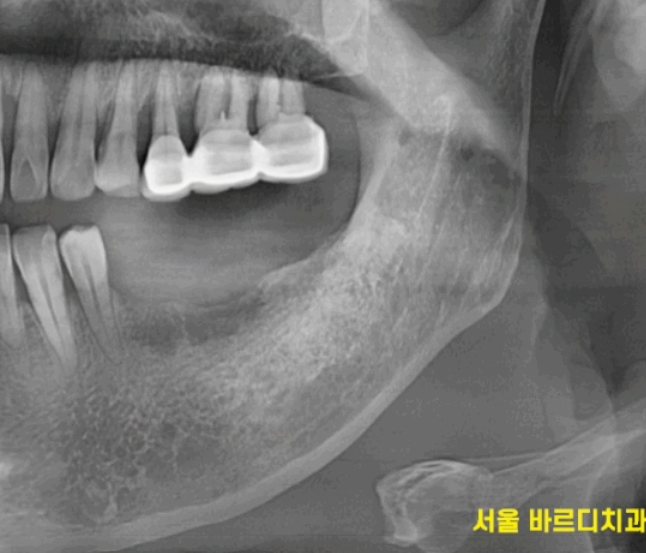

상일동역 치과 수술 직후의 사진입니다.

사진을 보시면 나사가 하나 들어간 것을

확인하실 수 있는데요.